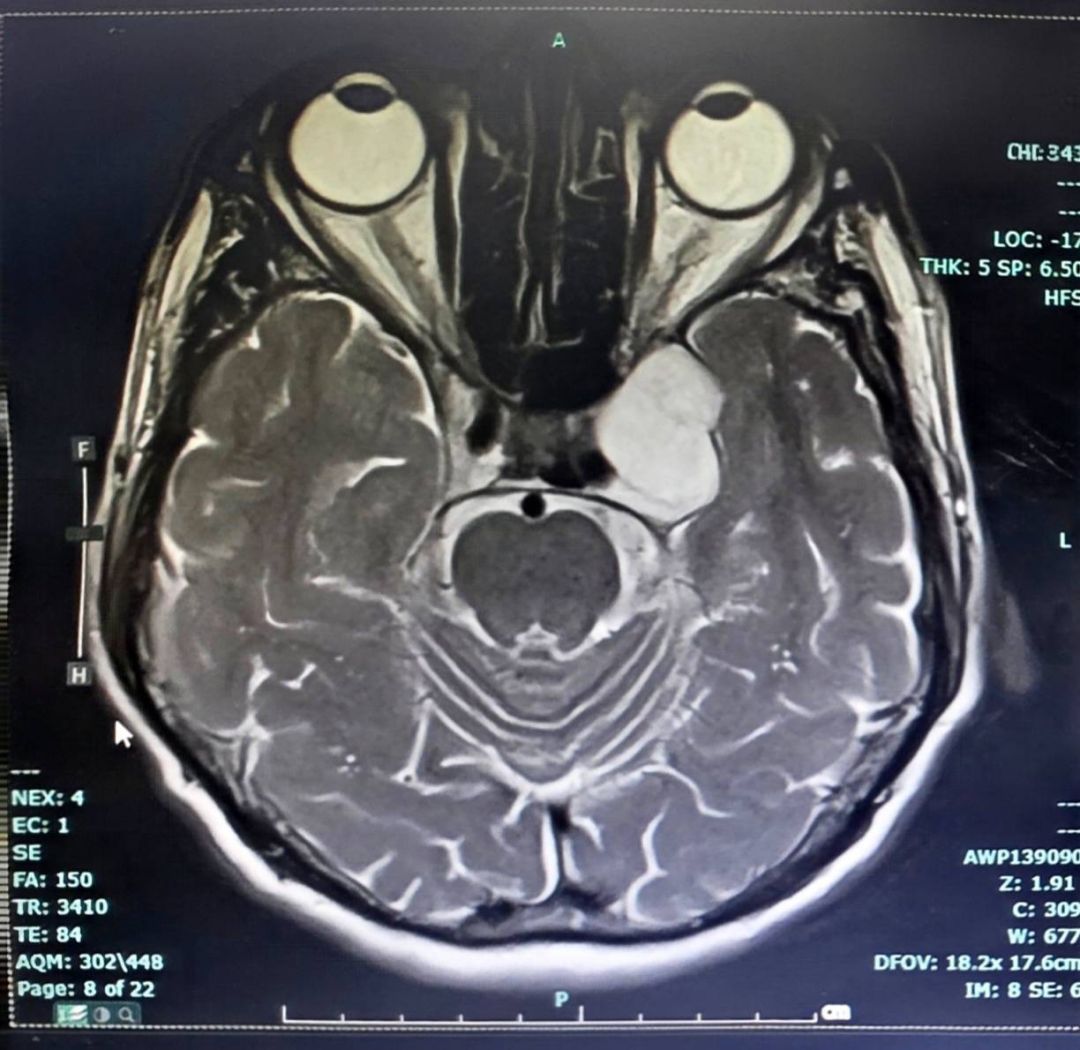

วันที่ 26 มีนาคม 2569 เพจเฟซบุ๊ก โรงพยาบาลลำปาง Lampang Hospital โพสต์ข้อความประสบความสำเร็จในการรักษาผู้ป่วย ความว่า ในวันที่ 24 มีนาคม 2569 โรงพยาบาลลำปาง ประสบความสำเร็จในการผ่าตัดเนื้องอกฐานสมอง (Skull Base Surgery) บริเวณโพรงไซนัสคาเวอร์นัส (Cavernous Sinus Tumor) ด้วยเทคนิค Endoscopic Transorbital Approach (ETOA) ซึ่งเป็นการผ่าตัดผ่านกล้องส่องทางเบ้าตา

ซึ่งจัดเป็นการผ่าตัดแผลเล็ก (Minimal Invasive Surgery) เป็นเทคโนโลยีศัลยกรรมขั้นสูงที่ช่วยลดการบาดเจ็บต่อสมองและโครงสร้างสำคัญ เมื่อเทียบกับการผ่าตัดแบบเปิดกะโหลกขนาดใหญ่ และนับได้ว่าเป็นการผ่าตัด ETOA เพื่อผ่าตัดเนื้องอกสมอง สำเร็จเป็นเคสแรกของเขตสุขภาพที่ 1 กระทรวงสาธารณสุข

การผ่าตัดดำเนินการโดย นพ.เอื้ออังกูรยิ์ สิทธิมงคล ศัลยแพทย์ระบบประสาท โรงพยาบาลลำปาง การผ่าตัดเป็นไปอย่างราบรื่น สามารถนำก้อนเนื้องอกออกได้สำเร็จ หลังผ่าตัดผู้ป่วยฟื้นตัวดี และสามารถกลับมาใช้ชีวิตประจำวันได้ตามปกติ